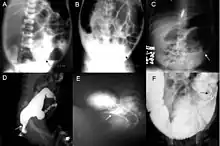

O diagnóstico definitivo é feito por biópsia por sucção do segmento estreitado distalmente.[26] Um exame histológico do tecido tem por objetivo mostrar a falta de células nervosas ganglionares. As técnicas de diagnóstico envolvem manometria anorretal,[27] enema baritado e biópsia retal. A biópsia retal por sucção é considerada o padrão ouro internacional atual no diagnóstico da Doença de Hirschsprung.[28]

Exames radiológicos também podem ajudar no diagnóstico.[29] A cineanografia (fluoroscopia do meio de contraste passando pela região anorretal) auxilia na determinação do nível dos intestinos afetados.[30]